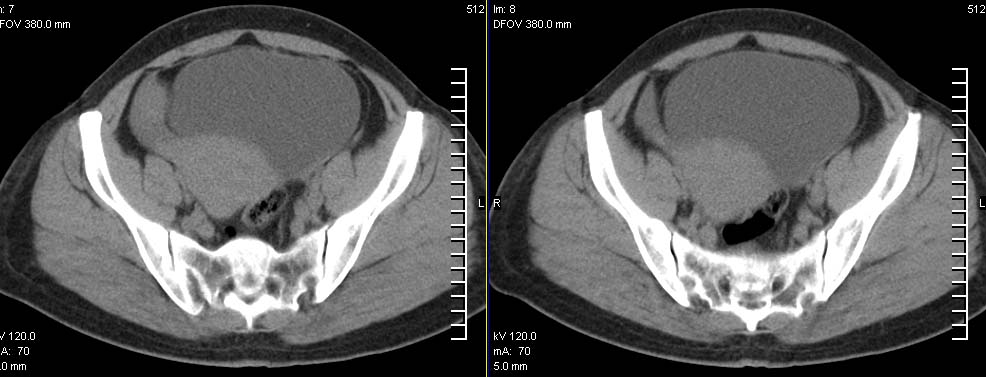

标题: CT9722:卵巢巨大占位,约10*18*21CM大小 [打印本页]

标题: CT9722:卵巢巨大占位,约10*18*21CM大小

卵巢巨大占位,约10*18*21cm大小

卵巢囊腺瘤可能性大.可见低密度

考虑:右侧卵巢囊性瘤可能性大 建议增强扫描。

肿瘤的密度有点高.和子宫差不多?且和子宫相连呢?我考虑来源于子宫,子宫巨大子宫肌瘤可能性大!(局部有坏死?)

考虑来源于卵巢的巨大占位,良性可能性大,内可见坏死区,建议强化检查。

右侧卵巢囊性瘤可能性大 ,5楼,密度不一样,是窗调得太宽

囊腺瘤不管是浆液性,还是黏液性的,液体成分应该占的比例很大吧!!这个病灶其实是个实性肿块,更看不到囊腺瘤所能见到的分隔??请笔者提供ct值?望大家再仔细分析??

右侧卵巢的巨大占位,病灶大部分呈实性,以恶性可能大。

右侧附件区巨大囊性肿块,边缘光滑,密度较高,左侧缘由多个低密度区,首先考虑囊腺瘤可能。